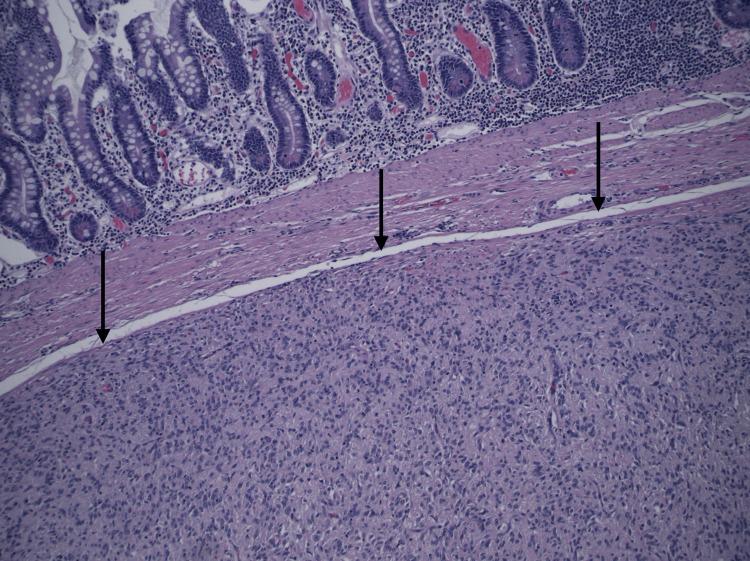

Gastrointestinal stromal tumors (GISTs) are rare in young individuals and typically affect older adults. We present the case of a previously healthy male who presented with severe hematochezia, fatigue, and dizziness. Colonoscopy did not demonstrate any colonic mass. CT of the pelvis with contrast revealed a pelvic mass measuring 7.4 cm. Biopsy confirmed a low-grade mixed-type GIST of the terminal ileum. Surgical resection was successfully performed. Histopathological analysis further characterized the tumor, and the patient was discharged with consideration of adjuvant imatinib therapy. This case underscores the importance of thorough diagnostic evaluation and multidisciplinary management for atypical presentations of gastrointestinal bleeding in young patients.

摘要

胃肠道间质瘤(GISTs)在年轻人中较为罕见,通常影响老年人。我们报告一例既往健康的男性病例,该患者出现严重便血、疲劳和头晕。结肠镜检查未发现任何结肠肿物。盆腔增强CT显示一个7.4厘米的盆腔肿物。活检证实为回肠末端低级别混合型GIST。成功进行了手术切除。组织病理学分析进一步明确了肿瘤特征,患者出院时考虑接受辅助伊马替尼治疗。该病例强调了对年轻患者非典型胃肠道出血表现进行全面诊断评估和多学科管理的重要性。